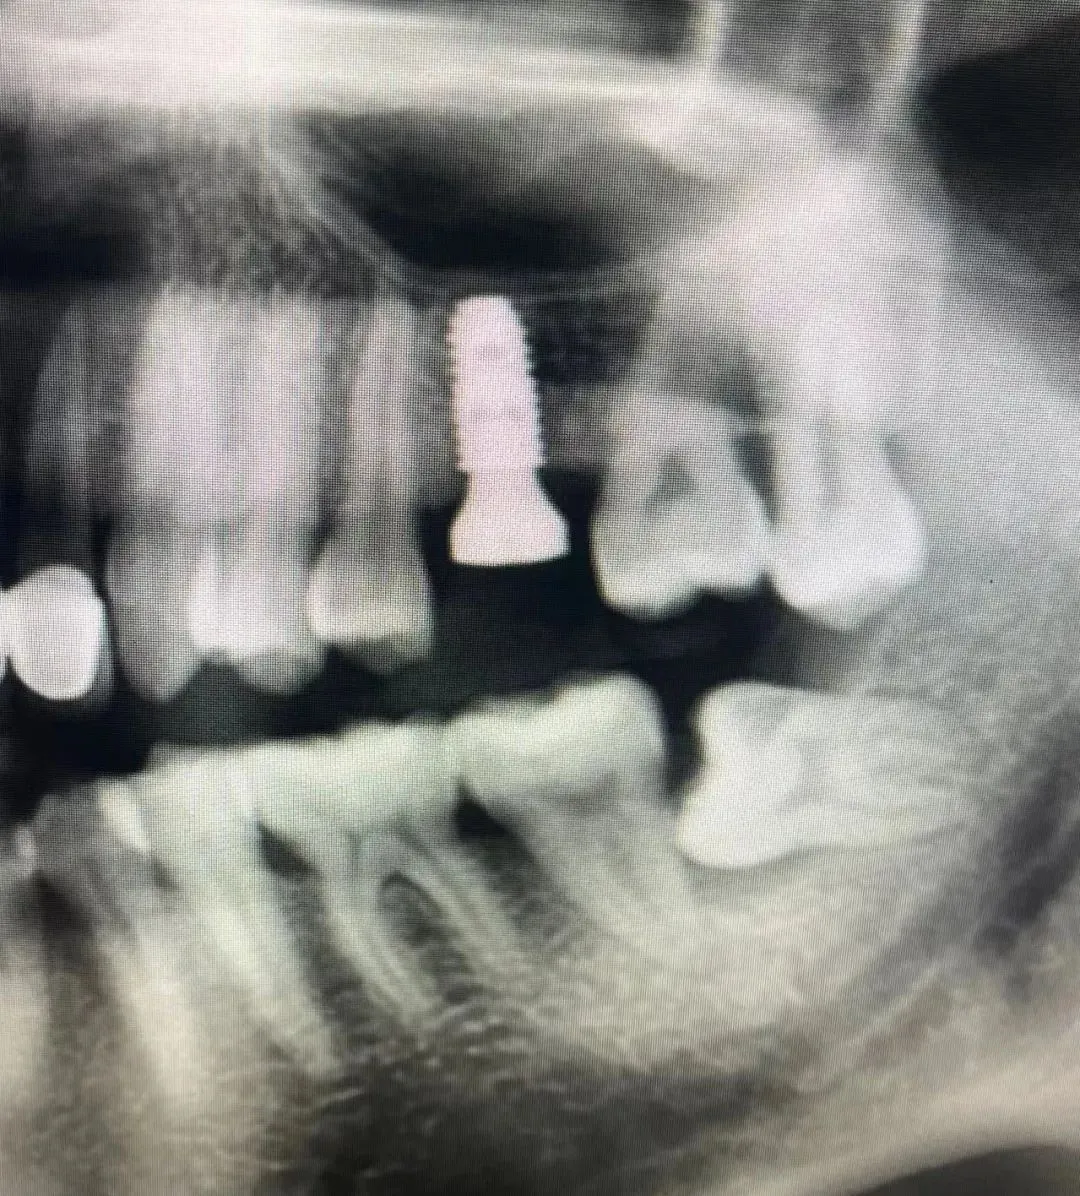

7、种植影像学分析;可以获得骨高度 ,骨宽度信息 ,甚至可以模拟种植体植入位点

六、学员回家后部分病例